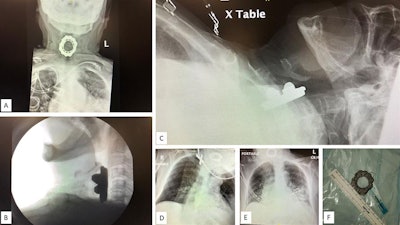

(A) Anteroposterior chest radiograph displaying a spinning top toy in the woman's hypopharynx. (B) Upright lateral neck radiograph. (C) Supine lateral neck radiograph. (D) Wide-angle anteroposterior neck radiograph. (E) Wide-angle anteroposterior neck radiograph. (F) Extracted toy with 3-cm diameter. Images courtesy of Dr. David Gerth. Licensed under CC BY-NC 4.0.Complicated by dementia

The woman was placed under general anesthesia to avoid erratic movements that could result in puncturing her esophagus. An otorhinolaryngologist surgeon used direct laryngoscopy and angled forceps for the extraction. Rapid sequence induction without application of cricoid pressure was used due to the position of the object, which was a spinning top toy, they wrote.